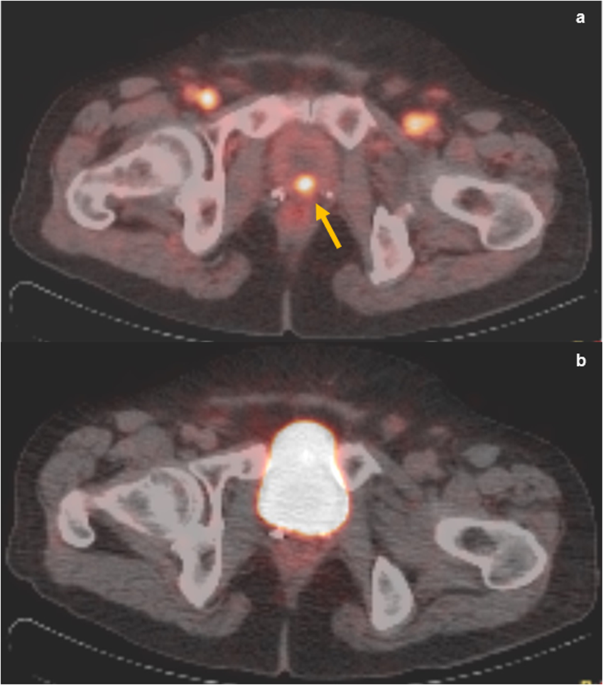

Psma Pet Ct In Initial Prostate Cancer Staging Nature Reviews Urology

Top Row A Psma Pet Ct Left And Ct Right Images Demonstrate Download Scientific Diagram

68 Ga Psma Pet Ct Identified Solitary L5 Metastasis In Patient With Download Scientific Diagram